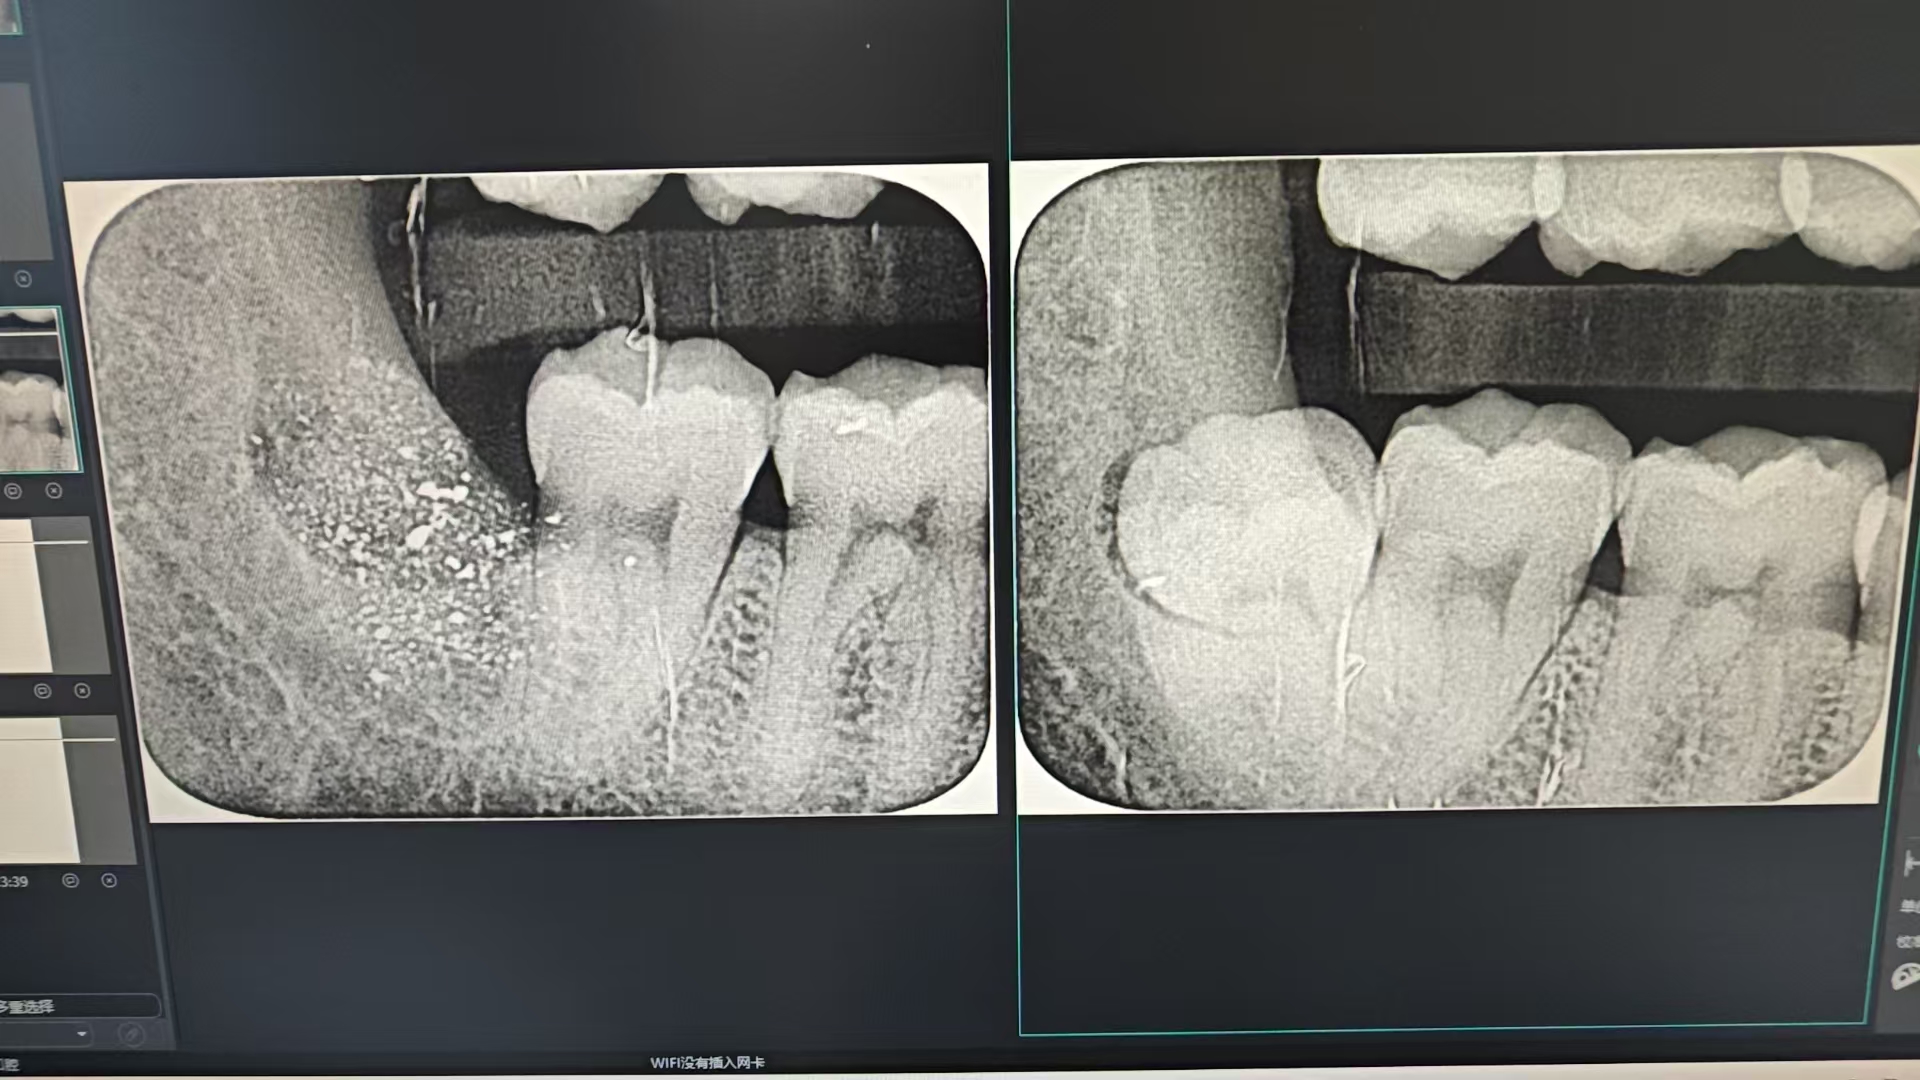

小牙片(比如看蛀牙深度、牙根情况):单次检查的辐射量大约只有 5 微西弗(μSv)。这是什么概念?坐飞机 1 小时,身体接受的宇宙辐射大概也是 5μSv—— 也就是说,拍一张小牙片的辐射,和坐 1 小时飞机差不多!

全景片(看全口牙齿排列、颌骨情况):辐射量稍高,但单次也只有 9-24μSv。举个更贴近的例子:香蕉本身含有天然放射性物质钾 - 40,吃 1 根香蕉大概会摄入 1μSv 的辐射。拍一次全景片的辐射,相当于吃 10-24 根香蕉的量,是不是听起来没那么吓人了?

CBCT(锥形束 CT,看种植牙、复杂阻生智齿等):辐射量相对更高,但也分 “小视野” 和 “大视野”。小视野 CBCT(只拍局部)大约 84μSv,相当于做一次胸部 X 光(约 100μSv);大视野 CBCT(拍全颌骨)大约 212μSv,相当于 10 天的自然本底辐射(我们每天呼吸、晒太阳,自然环境中的辐射大约 20μSv / 天)。